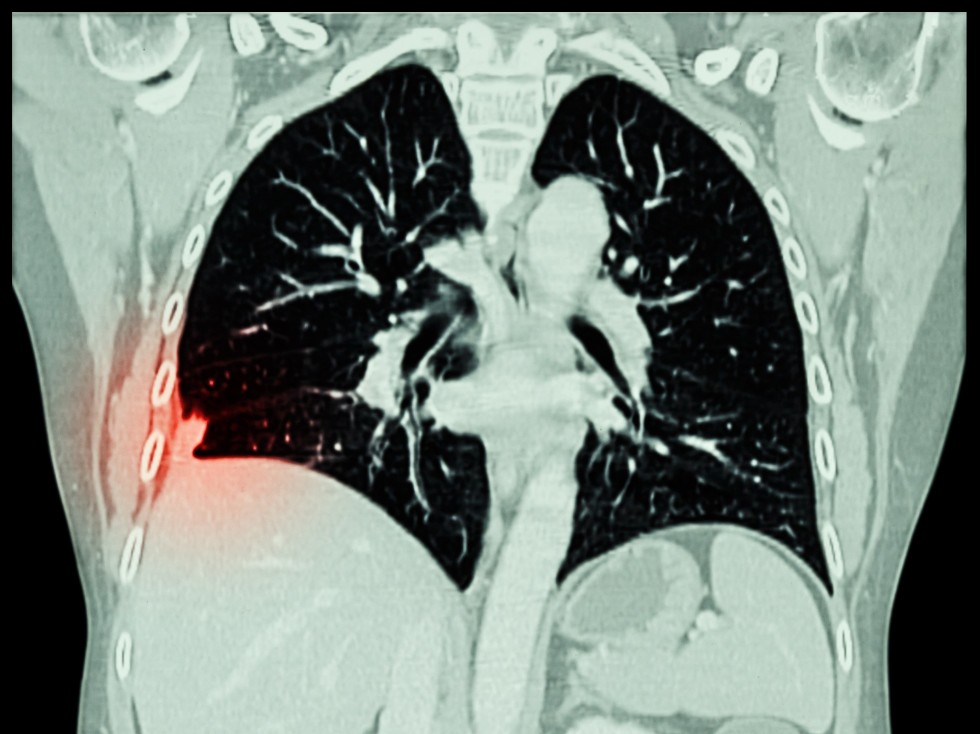

A CT of the chest is used to take high-resolution pictures of the lungs, allowing for the detection of abnormal spots called nodules. These nodules usually are too small to be seen on a chest X-ray. Studies show that low-dose CT screening greatly increases the likelihood of detecting lung cancer at an earlier and more curable stage than chest X-rays. According to researchers:

• Using CT, nodules were detected three times as often as on chest X-rays.

• Malignant tumors were detected four times as often as on chest X-rays.

• Stage I (the earliest stage of invasive lung cancer) malignant tumors were detected six times as often as on chest X-rays.

• Malignant tumors detected using CT were substantially smaller, meaning they were detected earlier, than those detected on chest X-rays.